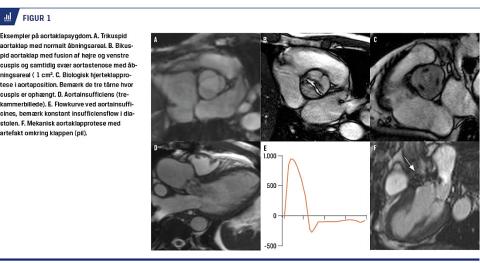

AORTASTENOSE

AS er hyppig hos ældre patienter med trikuspid aortaklap (1-2% over 65 år). Hos patienter med bikuspid aortaklap (0,5-1,0%) opstår AS tidligere i livet og med højere incidens (og evt. aortainsufficiens (AI)), og patienterne må ofte opereres tidligere. Med CMR visualiseres forkalkninger (f.eks. på klapper) ikke så godt som med ekkokardiografi og CT, men CMR kan benyttes til visualisering af klappen og vurdering af stenosegradient ved suboptimalt ekkovindue (Figur 1A + B), om end man med CMR undervurderer stenosegraden ud fra ligevægtsligningen. Koronarpatologi vurderes med koronarangiografi eller koronar-CT da man med CMR ikke kan visualisere koronarkar, med CMR kan man derimod foretage myokardieperfusionsskanninger [6]. CMR benyttes rutinemæssigt til opfølgning af patienter med bikuspid aortaklap (Figur 1B), hvor vurdering af ledsagende medfødt hjertesygdom, herunder ofte hypoplastisk aortabue og coarctatio, er nødvendig. Hos disse ofte yngre patienter ønsker man at følge aorta ascendens’ dimensioner grundet risiko for aortadissektion uden brug af ioniserende stråling (jf. bikuspid aortaklap-relateret aortopati). Man undersøger klappens morfologi og venstre ventrikels (LV) vægtykkelse, størrelse og kontraktile og diastoliske funktion [1]. Et aortaklapåbningsareal < 1,0 cm2 betragtes som udtryk for svær AS [7-10]. Ledsagende iskæmisk hjertesygdom kan bedømmes med gadoliniumteknik, og i forskningssammenhæng vurderer man diffus myokardiefibrose, der er et dårligt prognostisk tegn og ofte ses ved AS særligt i den basale (mitralklapnære) del af LV-myokardium [11, 12].

Mekaniske klapper vil give mindre billedartefakter (Figur 1F), og fraset ældre »ball-in-cage-klapper« kan klapperne problemfrit CMR-skannes (Tabel 1). Biologiske klapper evalueres som native (Figur 1C). Randlækage (insufficiens omkring syringen) kan være betydende, og i tvivlstilfælde benyttes CMR undertiden til vurdering af ReVol. Patienter, der er opereret for bikuspid aortaklap, vil ofte blive fulgt med CMR, også selvom aorta ascendens-dilatation umiddelbart er velrekonstrueret, da man af og til ser aneurismedannelse distalt for den indsatte rørprotese. Patienter med loop recorders kan skannes, og patienter med pacemakere kan oftest skannes især på korrekt indikation, man må blot huske, at pacemakeren skal indstilles før og efter skanningen. Der er primært problemer med non-MR-kompatible pacemakere og implanterbare kardioverterdefibrillatorenheder, cochleaimplantater, neurostimulatorer og neuro-coils [30].